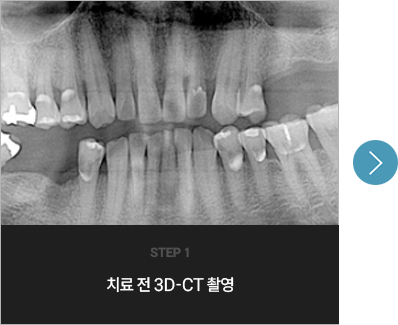

I      네비게이션 임플란트를 한 사례      I

치료 기간 : 2023.02.21 ~ 2023.11.10

* 상기 사례의 경우, 해당 의료기관에서 진료를 한 환자분의 동의를 얻어 사용되었습니다. * 치료 전후의 사진은 동일 인물과 동일한 조건에서 촬영 되었음을 알려드립니다.

* 모든 수술 및 시술은 개인에 따라 부작용고지 : 임플란트치료는 치료 후 감염, 염증,

연조직합병증, 출혈, 감각이상 등의 부작용이 있을 수 있습니다.

의료진과 충분히 상의 후 신중하게 결정하시기를 바라겠습니다.